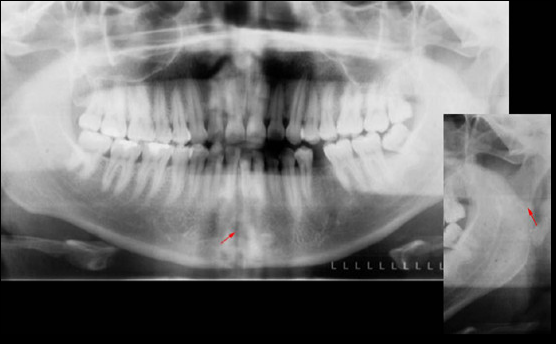

Caso N° 218: FRACTURA MANDIBULAR

Paciente de 32 años acude a la consulta radiológica post accidente automovilístico por presentar múltiples contusiones. Al examen extraoral el paciente refiere dolor a la palpación de la región mentoniana, asi como de la zona geniana del lado izquierdo, presentando limitación a la apertura. En la radiografía panorámica (fig.1) podemos observar un trazo de fractura de forma vertical localizada en la sinfisis mentoniana que va desde el reborde alveolar hasta la basal mandibular, ademas de una linea radiolúcida de forma oblicua localizada a nivel subcondilar del lado izquierdo. En la radiografía posteroanterior tipo Towne (fig.2) nótese un desplazamiento hacia medial del cóndilo mandibular del lado izquierdo, y en la radiografía oclusal (fig.3) confirmamos el trazo de fractura en la sinfisis mentoniana con desplazamiento de segmentos.